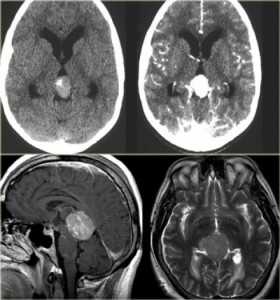

МРТ головного мозга. Сагиттальная и аксиальная Т1-взвешенные МРТ, аксиальная Т2-взвешенная МРТ и аксиальные КТ и Т1-взвешенная МРТ с контрастированием. Гигантоклеточная астроцитома с кальцификацией - внутрижелудочковая опухоль.

КТ и МРТ головного мозга. Аксиальные КТ, Т2-взвешенные МРТ и МРТ головного мозга с контрастировавшем. Вовлечение коры при олигодендроглиоме.